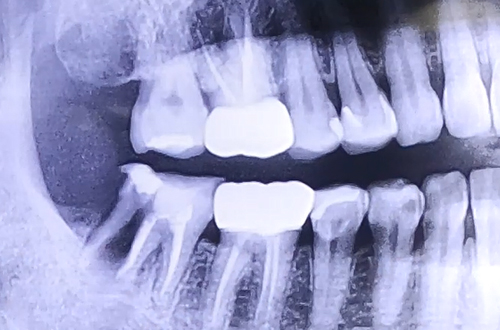

AFTER

치료 유형 발치 후 임플란트

치아에 엄청난 통증을 호소하며 급하게 내원해주신 환자분이십니다.

살펴보니 이미 오래 전에 치료가 다 되었다고 생각했던 충치 치료를 했던 치아가 크게 쪼개진 상태였는데요.